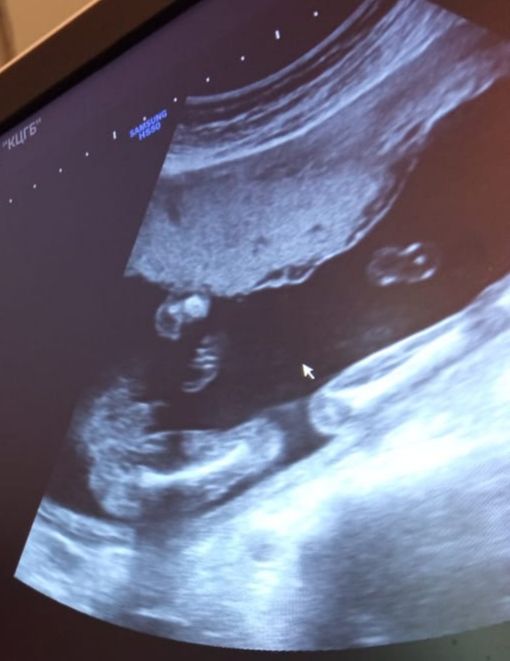

По узи 100% мальчик? Фото в посте

по этому фото непонятно. а так любой супер узист ошибиться может, у подруги один из самых топовых узистов СПб и на первом и на втором скрининге ошибся, на третьем он же увидел правильно уже.

Не очень понятно ,у девочки тоже довольно таки опухшие губки на фото ,может девочка ,переделать узи

Фото очень нечеткое,мне на экране показали в 16 недель там мошонка и писюн были знатные...а так и пуповина может быть и пельмешки иногда путают с яичками.посмотрите позже еще)))

elena, я вообще в надежде на девочку))) уже выкупила и вещи некоторые. Жду второго скрининга 🙈 Просто мне в три д не перевели фото именно половых органов, а для меня эти узи все тяжело распознаваемые. Я вроде вижу, что парень. И муж видит. А кому скинула фото, говорят, что не видят мужской писюн…

Елизавета, вот и я тут не вижу

Изображение нечёткое. Что-то торчит, а вот очертаний не видно🤷‍♀️